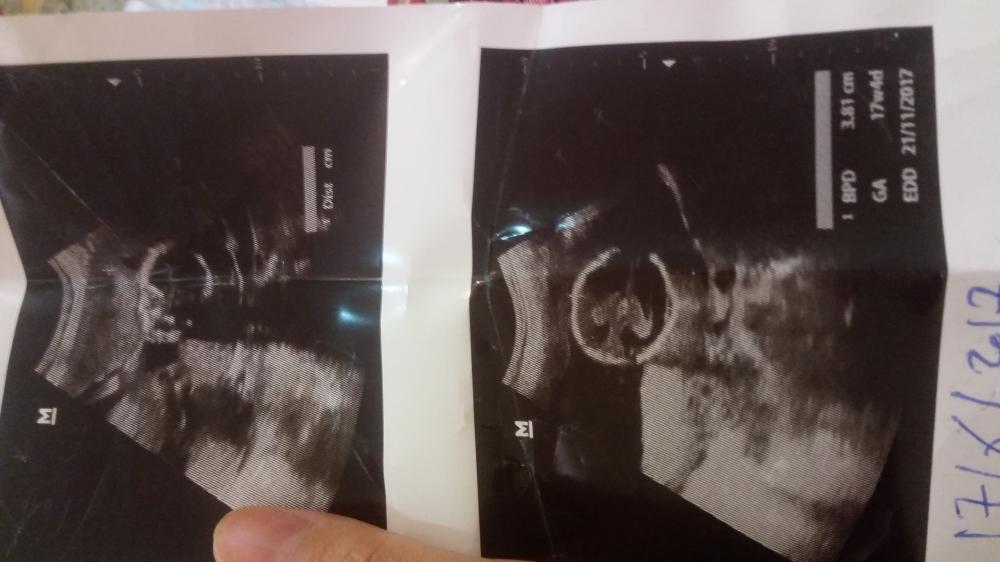

مدري هذي واضحه او لا